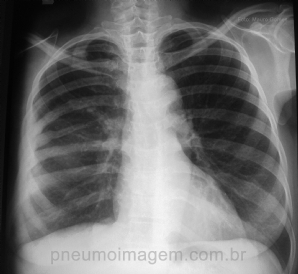

CASO CLÍNICO #34

Paciente se apresenta com dispneia. Você acha que a lesão apontada pela seta é a causa do sintoma? Deixe seus comentários abaixo. ***** Patient has dyspnea. Do you think the lesion of the arrow is the cause of the symptom? Write your comments below.